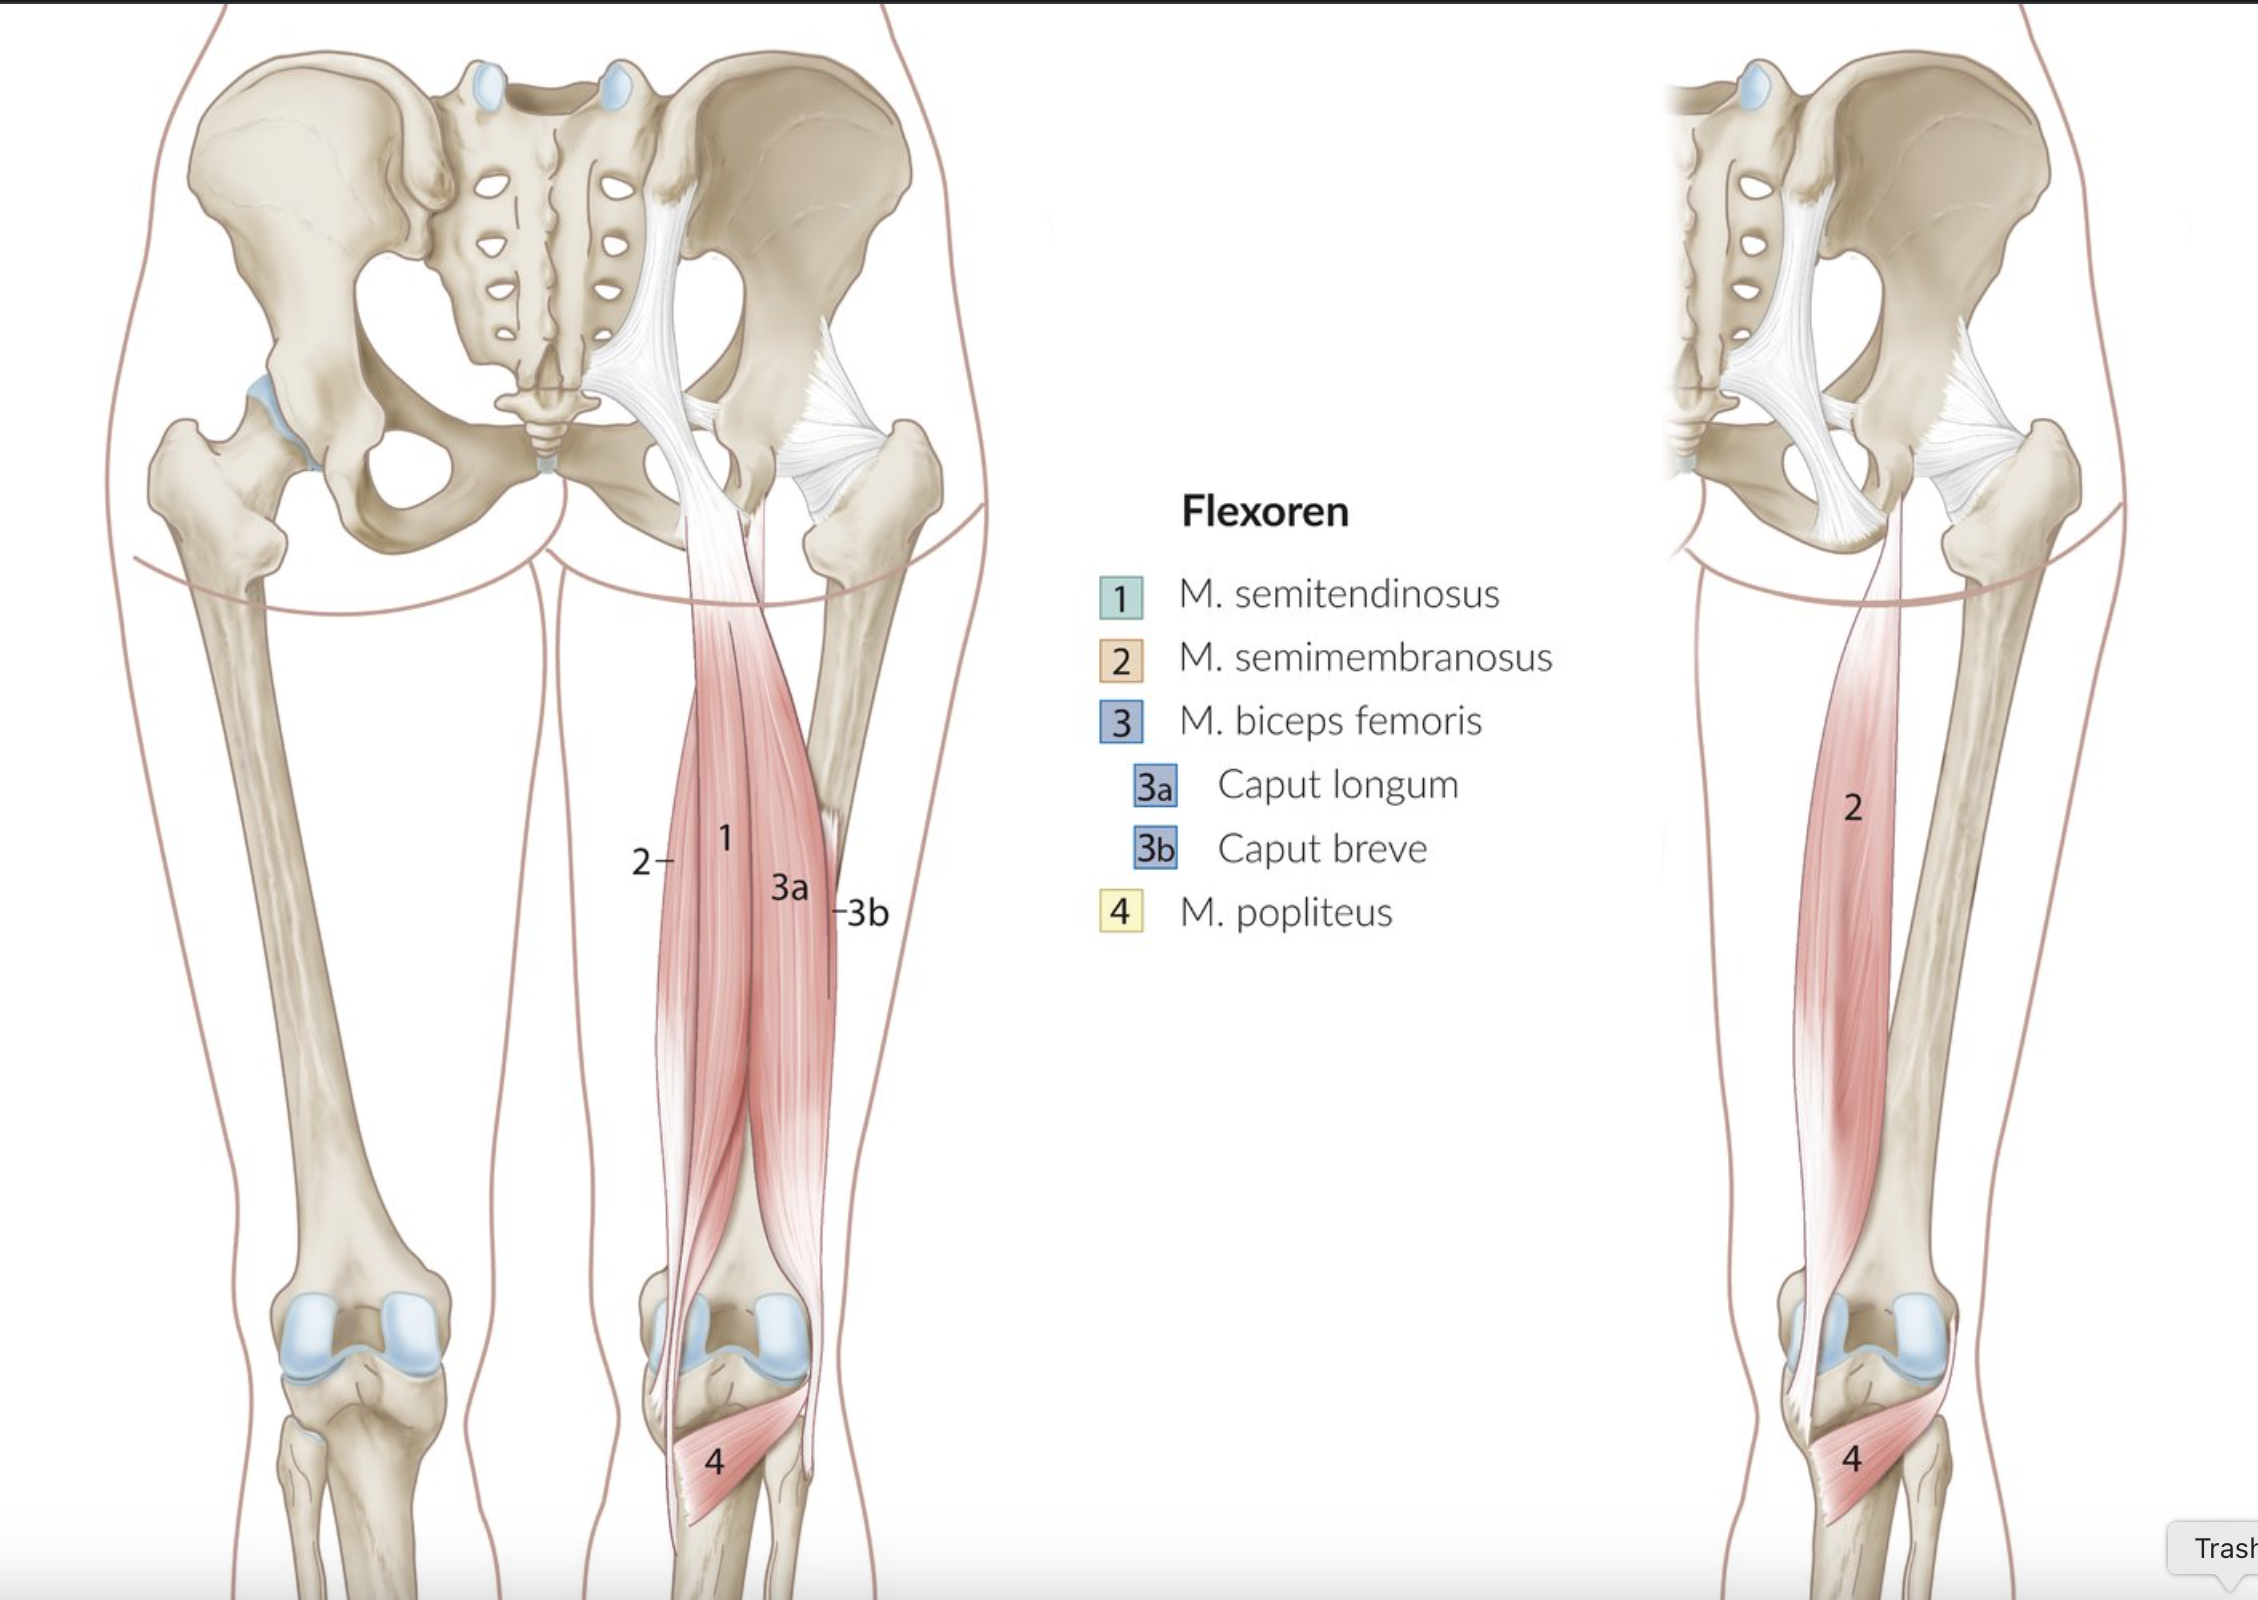

24. The knee joint is a compound joint that allows different movements depending on its position.

Which of the following muscles is involved in both flexion and external rotation of the knee joint?

A. Biceps femoris muscle

B. Gracilis muscle

C. Sartorius muscle

D. Semimembranosus muscle

E. Semitendinosus muscle